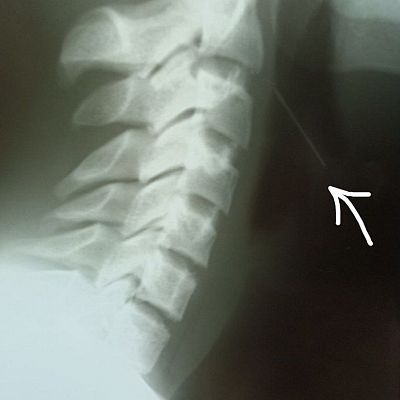

Родители с ним сразу отправились в больницу, сделали снимок (отчетливо видно инородное тело), и подростка отправили к нам, так как больница в соседнем округе не располагала возможностями для решения проблемы.